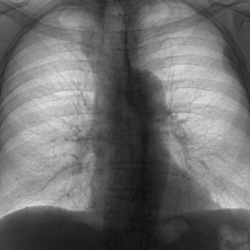

Добрый день. Пациент температурит пятый день, до 39. Терапевт аускультативно слышит и ослабление, и жёсткое дыхание, причём с 2-х сторон, ожидали пневмонию на снимке, но я не вижу. Хотела придраться...